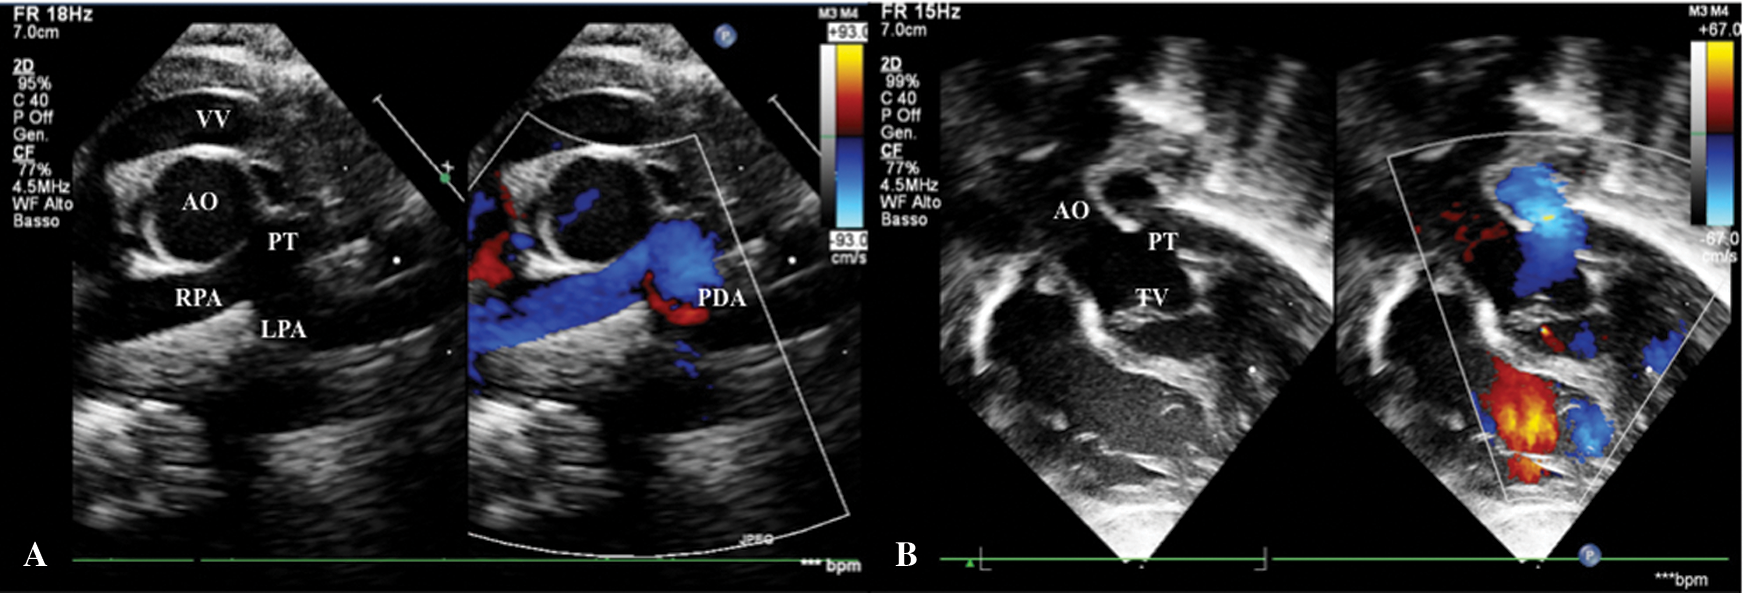

A female patient with prenatal diagnosis of CAT, born at term from eutocic delivery with 3.4 kg body weight and peripheral oxygen saturation was 85%. There were no associated extracardiac malformations. A sequential segmental echocardiographic analysis confirmed CAT Type I CE (Fig. 4B) with normal coronary artery anatomy, bicuspid semilunar truncal valve with mild insufficiency, and the presence of a small patent ductus arteriosus (PDA) (Fig. 4A) with left-sided unobstructed aortic arch. Additionally, echo detected a moderate dilatation of the vertical vein, without hemodynamic consequences (Fig. 4A).

Figure 4: A. Short-axis view shows CAT Type I CE, small patent ductus arteriosus in left pulmonary artery and dilated vertical vein. B. Subcostal view shows mild truncal valve insufficiency. AO: Aorta, LPA: Left Pulmonary Artery, PDA: Patent Ductus Arteriosus, PT: Pulmonary Trunk, RPA: Right Pulmonary Artery, TV: Truncal Valve, VV: Vertical Vein